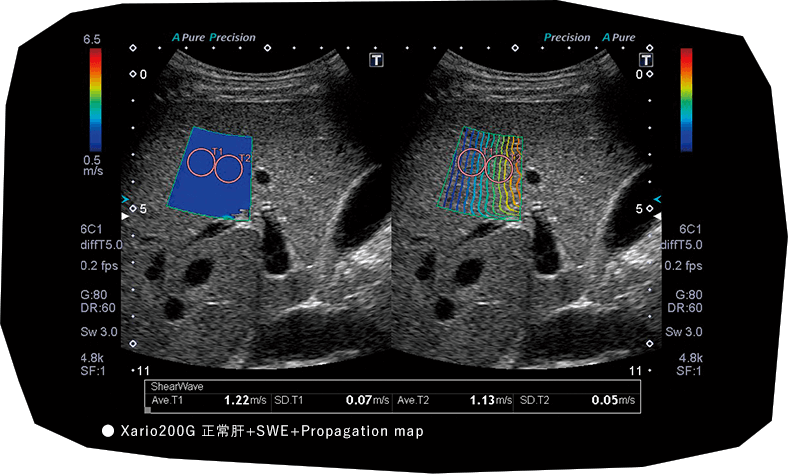

超音波のSWEは汎用機など、上位機種でなくても肝硬度が測れるようになりつつあるので、多くの現場で広く使われる可能性が高い。それによってエビデンスが集まってくれば、今後日本ではこちらを診断基準に採用するように移行するかなと思っています。

飯島

日本消化器病学会雑誌に総説を書いていますが、キヤノンの場合、上位機種はもちろん、汎用機種のXario 200 にもSWEは搭載されています。クオリティについても上位機種とほとんど変わらないと聞いています。また、どこを計測したら良いかがわかる、剪断波の伝搬状態を可視化したPropagation mapがあります。これは開業医の先生方が使いやすい機能だと思いますので、今後の状況はかなり良くなる見込みがありますね。